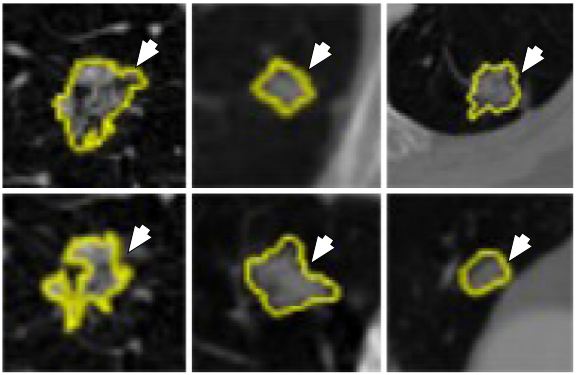

The high-content screening (HCS) technologies have enabled large scale imaging experiments for studying cell biology and for drug screening. The ML-based algorithms available are optimized for mammalian cells and not for tiny organisms such as yeast. The DL approaches that learn feature representations directly from pixel intensity values have currently dominated object recognition challenges worldwide. In this study, the approach has been to combine CNN with multi-instance learning (MIL) in order to segment microscopy images using only whole image level annotations (52). In MIL, the supervised algorithm trains not from single instances rather a group of instances at a time. The similarity between the pooling layer and the MIL aggregation function is exploited here, where features in convolutional layers correspond to instance features in MIL. If class specific feature maps are treated as bags of instances, then the classical approaches in MIL can be generalized to global pooling layers over these feature maps. The CNN produces an image level classification over images of arbitrary size and varying number of cells through a MIL pooling layer. The individual cells are classified by mapping the probabilities in class specific feature maps back to the input space. The pre-softmax activations of specific output nodes are back-propagated through a classification network to generate Jacobian maps with respect to specific class predictions. The segmentation masks are generated by thresholding the sum of the Jacobian maps along the input channels. Loopy belief propagation (reference #10 in (52)) is used to improve the localization of cellular images with respect to segmentation masks. The DL framework consisted of seven convolution layers, four pooling layers, one MIL pooling layer and one fully connected layer. A total of three types of datasets were used. Data was collected from nine categories of MNIST handwritten digits dataset. From each category, 50 images were used for training and 10 images were used for testing. The second dataset consisted of MFC-7 breast cancer cells available from the Broad Bioimage Benchmark Collection. A total of 300 microscopic images were used for training and 40 images were used for testing. Cell data was also collected from yeast GFP collection. A total of 2200 images were used for training and 280 images were used for testing. The equivalent model is given in Figure 28. The segmentation is output is shown in Figure 29. The test error for MNIST dataset was 0%. The highest accuracy for yeast dataset and breast cancer dataset across all classes was 0.96 and 0.97 respectively. The results showed considerable increase in accuracy across all datasets. The system should be validated with larger breast cancer dataset to increase its clinical value.

Figure 28Model depiction deep multiple instance learning.

Figure 29Segmentation using FCN-MIL pooling methodology. (a) Shows the Jacobian maps, (b) shows thresholding, (c) denoising using loopy bp and (d) segmentation outlines (reproduced with permission from (51)).